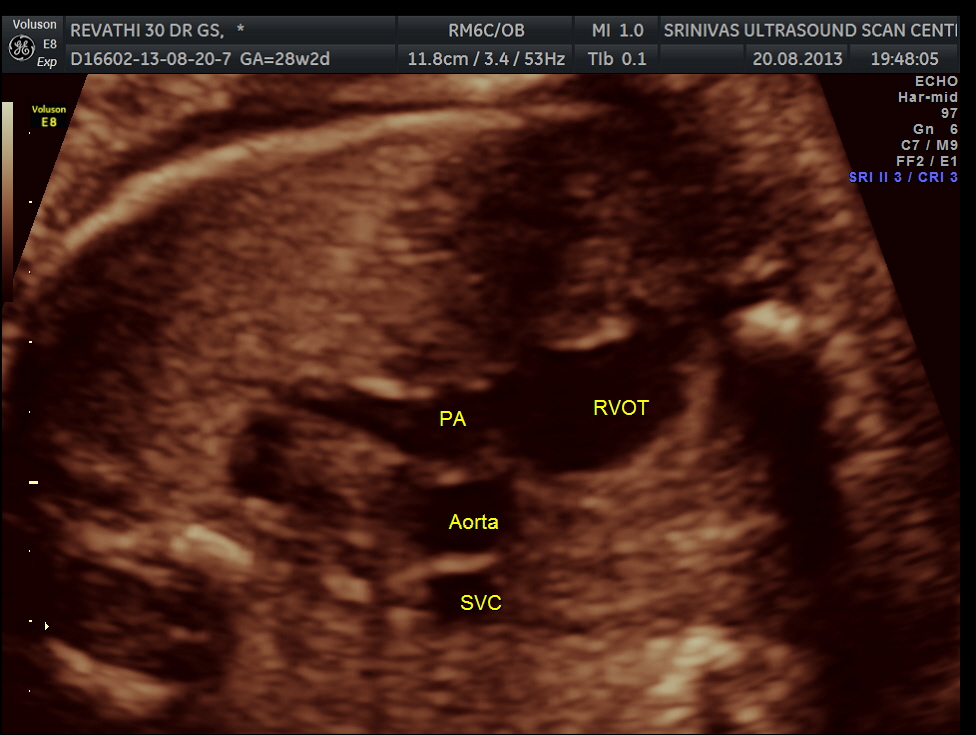

next is the normal outflow tracts and the normal 3 vessel view and the normal arches.

here we can see the pulmonary artery with its two branches arising from the lower (left) ventricle .and the aorta arising from the anterior (right ) ventricle.